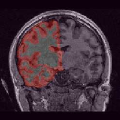

To compare the proposed approach to the mSENSE333SENSE reconstruction implemented by the Siemens scanner, software ICE, VB 17. one, Fig. 1 illustrates coronal anatomical slices reconstructed with both algorithms while turning off the temporal regularization in 4D-UWR-SENSE, so resulting in the so-called 3D-UWR-SENSE approach. Red circles clearly show reconstruction artifacts and noise in the mSENSE reconstruction, which have been removed using our 3D-UWR-SENSE approach. Comparison may also be made through reconstructed slices for and , as well as with the conventional acquisition (). This figure shows that increasing generates more noise and artifacts in mSENSE results whereas the impact on our results is attenuated. Artifacts are smoothed by using the continuity of spatial information across contiguous slices in the wavelet space. Depending on the used wavelet basis and the number of vanishing moments, more or less (4 or 8 for instance) adjacent slices are involved in the reconstruction of a given slice. For instance, using Symmlet filters of length 8 (4 vanishing moments) as in the conducted experiments here, 8 adjacent slices are involved in reconstructing a given slice. However, it is worth noticing that the introduced smoothing is anisotropic, in contrast to standard Gaussian smoothing that could be applied to anatomical data. Fig. 1 also compares 3D-UWR-SENSE and mSENSE reconstructed slices when applying additional spatial smoothing to the later with a mm3 Gaussian kernel. Comparisons clearly show that, even at such low spatial smoothing level, mSENSE images suffer from a significant blur. Moreover, the artifact present at for mSENSE (left red circle) is spread out but not fully removed by applying isotropic spatial smoothing.

In order to evaluate the impact of such smoothing, classification tests have been conducted based on images reconstructed with both methods. Gray and white matter classification results using the Morphologist 2012 pipeline of -MRI toolbox of Brainvisa software444http://brainvisa.info at and are compared to those obtained without acceleration (i.e. at ), considered as the ground truth. Displayed results in Fig. 2 show that classification errors occur due to reconstruction artifacts for mSENSE, especially at . Results show that the gray matter is better classified using our 3D-UWR-SENSE algorithm especially next to the artifact into the red circle (Fig. 2 []), which lies at the frontier between the white and gray matters. Moreover, reconstruction noise with mSENSE in the centre of the white matter (left red circle in Fig 2 []) also causes miss-classification errors far from the gray/while matter frontier. However, at and classification performance is rather similar for both methods, which confirms the ability of the proposed method to attenuate reconstruction artifacts while keeping classification results unbiased.